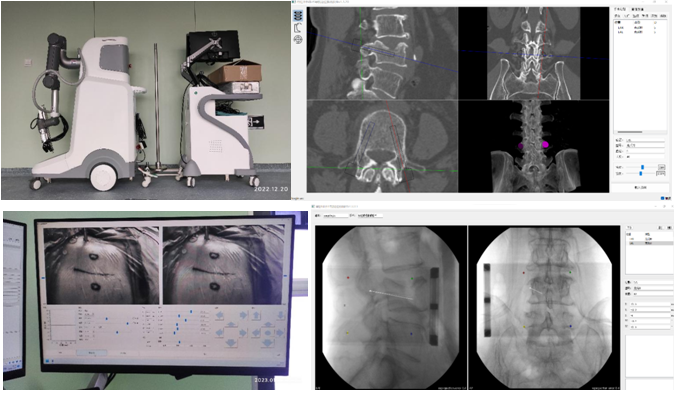

机器人辅助技术是脊柱外科手术向智能化、精准化、微创化发展的又一次飞跃。1月10日,刘时璋主任带领骨科团队精诚合作,在手术室、麻醉科及消毒供应室的鼎力协助下,成功开展欧美视频

首例机器人辅助局麻下“经皮球囊扩张椎体成形术(PKP)”治疗腰椎压缩性骨折。此例手术较传统的徒手穿刺更为精准、安全、高效,体现了数字医学与骨科智能化的融合发展。

经MRI及CT检查示:腰4椎体压缩性骨折。经专家讨论后,医疗团队拟采用机器人辅助,局麻下行经皮球囊扩张椎体成形术。经过精密的仪器调试和配准,术前进行了反复的模型演练。刘时璋主任团队将患者的CT数据与机器人系统配准,工程师团队将事先规划好的个体化穿刺路径数据植入机器人系统。将术中的正侧位X线透视数据与CT数据融合后,机械臂按照术前规划路径,一次性穿刺成功,位置精准满意。